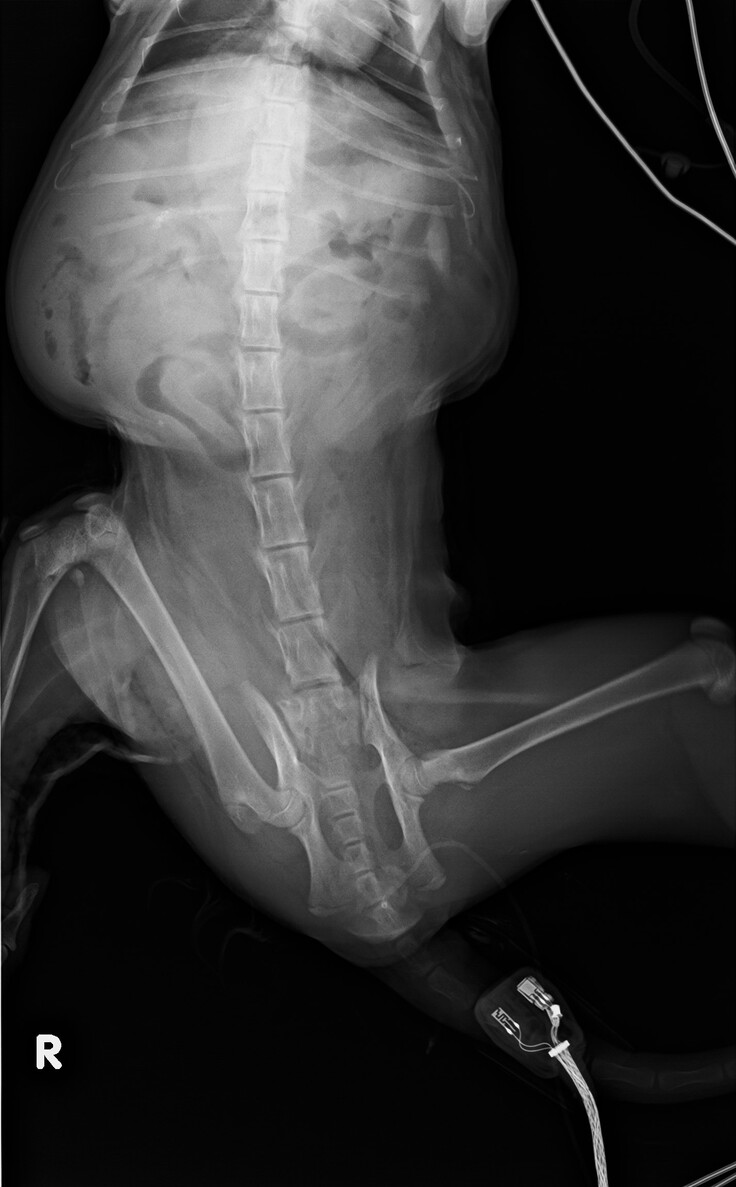

下半身を強くぶつけたようで、膀胱と右後ろ脚に大きなダメージがあり、手術が必要でした。

・膀胱損傷

・右後ろ脚骨折

4月11日、すぐに緊急手術していただき、膀胱は10日間ほどでカテーテルが外れ、自力でオシッコができるようになりました。

顔の腫れと鼻血は数日で落ち着きました。寄生虫がひどかったので駆虫していただきました。

4月20日、右後ろ脚の骨折を治すため、プレートで固定する手術を行いました。